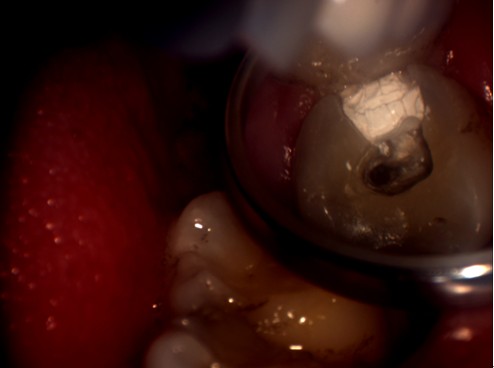

明美工程師在剛開始接觸牙科專用顯微鏡時,對這臺牙科專用顯微鏡有點陌生。牙科專用顯微鏡與其他的顯微鏡有點不同,1米多高的機身,沒有粗微調,調焦只能通過手動上下移動來實行。在安裝過程中遇到了很多技術上的難題,如顯微鏡的接口問題,這款顯微鏡的C接口并不是標準的C型接口,有點偏小。經過我們工程師專業(yè)的技術經驗及反復試驗,發(fā)現(xiàn)在它原有的接口的基礎上再接上準的C型接口,即接兩個C接口就能把顯微鏡相機安接裝上去。但是安裝上去并不能完解決此問題,還有成像方面的問題,由于它原有的C接口不是標準的C口,在實拍的時候,可以達到同步的效果,而且靜態(tài)拍攝圖片效果不錯,但在實際口腔內拍攝的時候圖像太暗,若只通過軟件調節(jié)后,亮度達到了,但是有點反光,通過和技術人員溝通后,發(fā)現(xiàn)那臺顯微鏡用的是一個普通的照明燈,亮度不可調,通過幾番周折后,通過調試后亮度問題終于解決。明美工程師在順利安裝完成了,楊主任對此效果表示滿意,亦對明美工程師的專業(yè)技術能力給予肯定。以下為顯微鏡相機實拍圖片:

顯微圖片

牙科顯微圖片